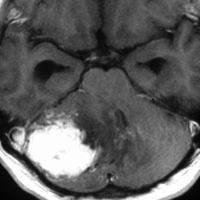

左右の写真は異なった患者さんのものです。両者ともに,大きな嚢胞(水たまり)を伴う小脳内部の小さな血管芽腫です。右の方に小さく白い塊(黄色の矢印)が見えるのですが,それだけが腫瘍で,濃い灰色に見える部分はのう胞といって液体がたまっているだけです。

これはとても(といっては何ですが比較的に)簡単な手術例です。小脳失調によるふらつきや水頭症よる頭痛と嘔吐などを出しますが,手術後に症状は改善します。

一般に小脳半球という場所にできたものは大きくても手術の成功率はとても高いです。小さいものでは場所と症状によってはガンマナイフなどの放射線治療も有効なことがあります。しかし,手術で摘出できるものは摘出した方が確実に治ります。